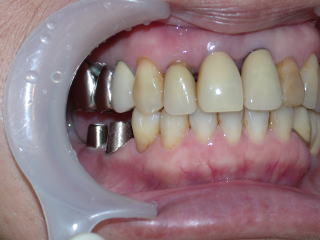

インプラントにカスタムアバットメント装着。

手前は通常通りメタルコア装着。

上部構造物ができました。

右下5番6番を装着しました。